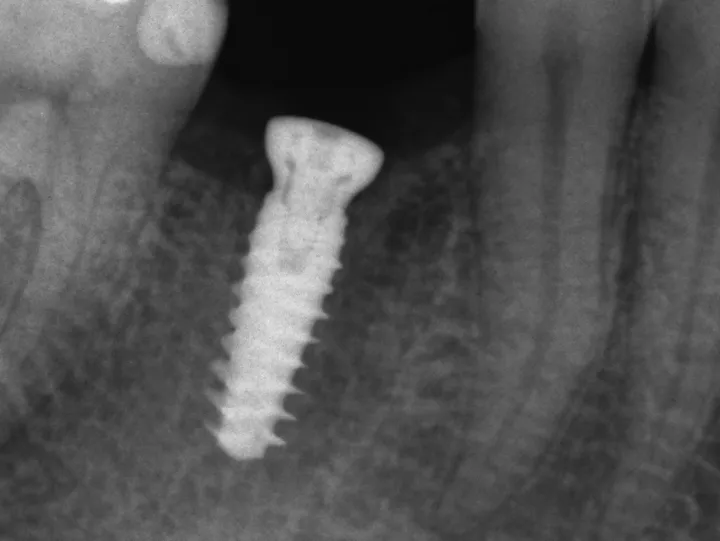

12. Après une période de cicatrisation de 12 semaines (qui s'est déroulée sans incident), le patient est venu pour les empreintes finales. Une radiographie a été prise et un remodelage osseux a été observé.